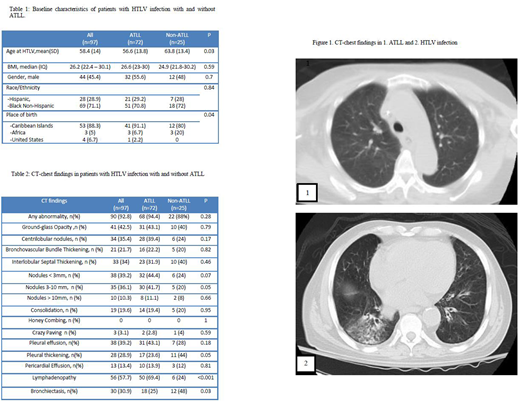

Results: A total of 97 patients (72 with ATLL and 25 with HTLV alone) were identified. Mean age at HTLV diagnosis was 58.4 years (range: 33-88), 54.6% were females, 72.2% were Black Non-Hispanics while 27.8% were Hispanic. 88.3% were from Caribbean origin. Smoking history was similar between ATLL and non-ATLL groups (12% vs 8%, p=0.07) with no cases of prior active TB infection. Abnormal CT chest findings were present in 92.8%, 94.4% and 88% for the total cohort, ATLL and non-ATLL patients.

Among patients with ATLL, 52.1% had acute and 43.7% had lymphomatous types; while only 1.4% and 2.8% had smoldering and chronic type. The most common CT chest findings were lymphadenopathy (50, 69.4%); followed by 3-10 mm nodules (32, 44.4%), ground-glass opacity, pleural effusion (31, 43.1% each), centrilobular nodules (28, 39.4%), thickening of interlobular septum (23, 31.9%) and bronchiectasis (18, 25%). Compared to the acute subtype, patients with lymphomatous subtype had higher rates of lymphadenopathy (83.9% vs 64.9, p=0.07) and lower rates of bronchiectasis (16.1% vs 35.1%, p=0.07).

Among patients with non-ATLL, HTLV infection was diagnosed at an older age (63.8 vs. 56.6 years, p=0.03); HTLV-associated comorbidities were found in 16 cases (64%). Of these, myelopathy was the most frequent (10, 40%), followed by strongyloides (4, 16%). After HTLV diagnosis, CT chest was indicated in 28% patients for otherwise unexplained respiratory symptoms and to evaluate lung nodules or other chest X-ray abnormalities in 24% of cases. Bronchiectasis was the most common finding (12, 48%) followed by pleural thickening (11, 44%), ground-glass opacity and thickening of interlobular septum (10, 40%, each). Persistent abnormalities on follow-up imaging were present in 86.7% of the cases. Among patients with HTLV infection, those with ATLL were more likely to have nodules and lymphadenopathy (41.7% vs 20%, p=0.05 and 69.4% vs 24%, p<0.001, respectively) while bronchiectasis and pleural thickening was more likely in patients without ATLL (48% vs 25%, p=0.03 and 44% vs 23.6%, p=0.05; respectively).

Conclusions: Pulmonary findings are highly prevalent in CT chest of patients with HTLV infection with and without ATLL. Bronchiectasis and pleural thickening was more frequently encountered in non-ATLL patients while lymphadenopathy and nodules were common finding in patients with ATLL. Pulmonary involvement in lymphoma is usually characterized by nodules and lymphadenopathy but patients with ATLL had a higher incidence of findings including ground glass opacities, bronchiectasis and interlobular septal thickening possibly due to their underlying HTLV infection. Based on this data, nodules and lymphadenopathy should be classified as ATLL involvement of the lung while other findings described here could be due to HTLV infection. These findings are important in staging and response criteria for ATLL.